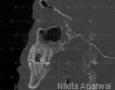

CBCT :

Yes